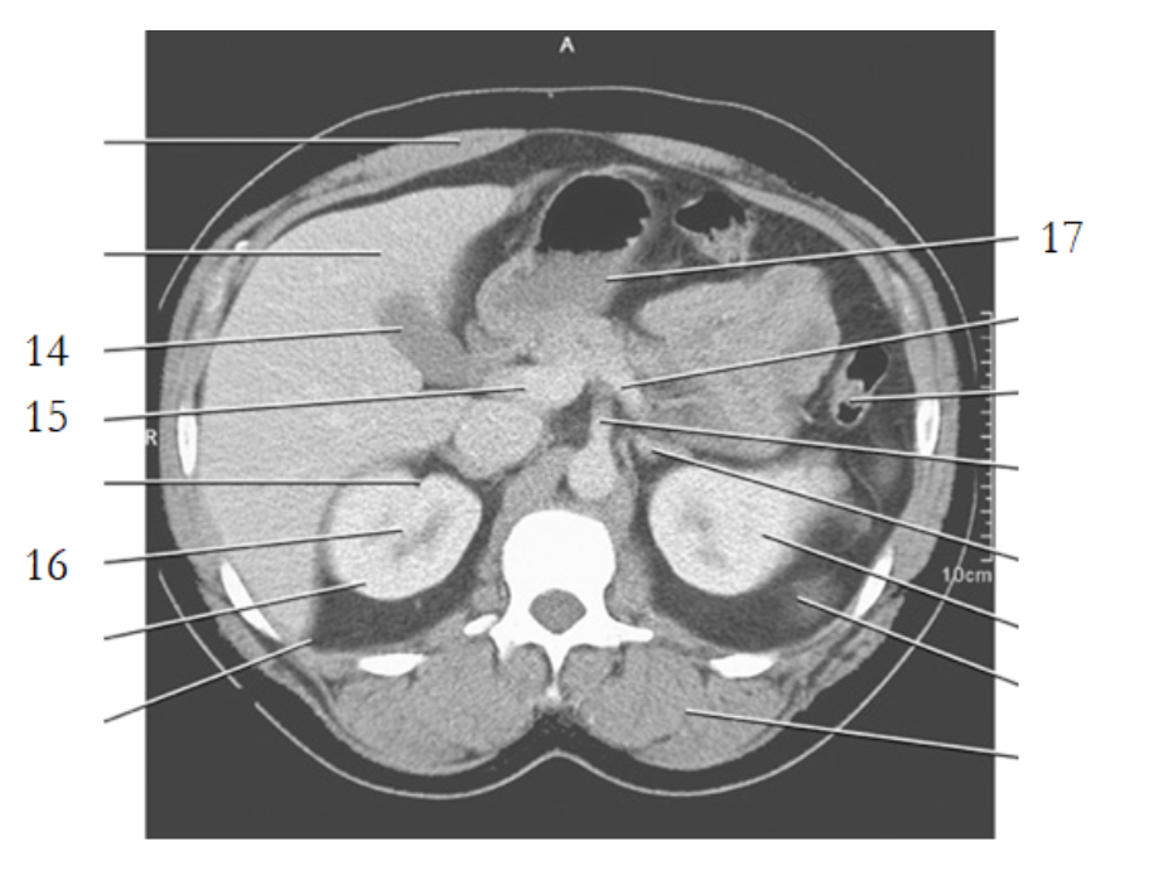

14

8

9

17

15

16

kidney

4

25

spleen